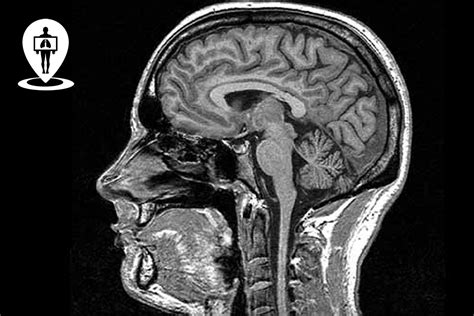

La diagnosi di demenza è un processo complesso che richiede la collaborazione di specialisti, tra cui geriatri, neurologi e psicologi. Il percorso diagnostico include la raccolta della storia clinica del paziente, una valutazione neuropsicologica e comportamentale, esami di laboratorio e tecniche di neuroimaging (come TAC e RMN dell'encefalo).